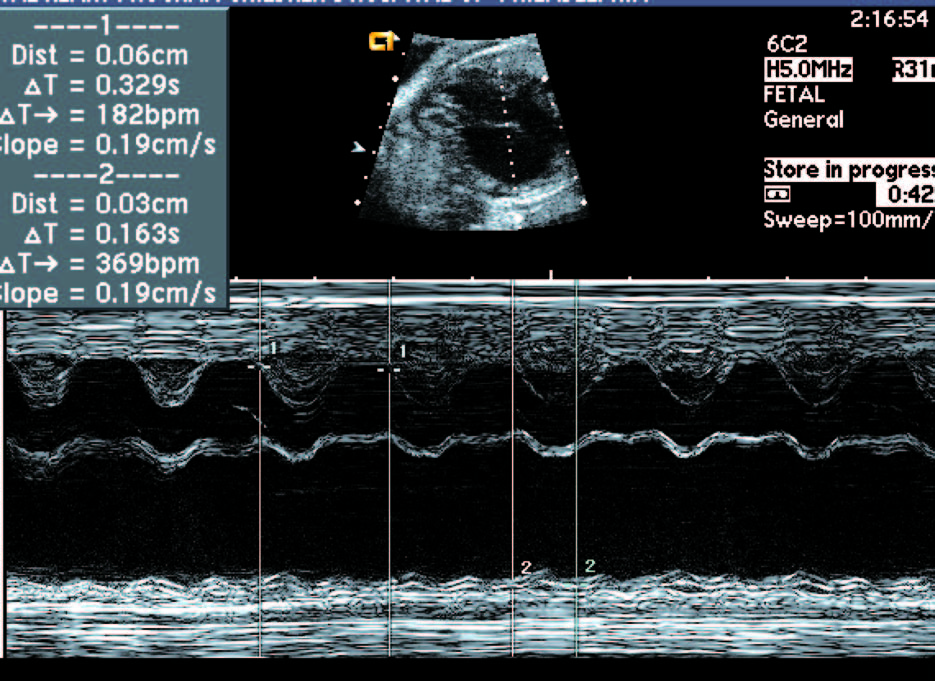

2.慢速心律失常:胎儿心率< 100 次/min, 持续时间>5 min,为心动过缓。

①完全性房室传导阻滞:即心房与心室之间电生理联系完全被打断,二者的收缩节律毫无关系。常在母体有自身免疫系统疾病时发生,预后差,常早期出现胎死宫内。图中病例可见心房率143 次/ 分,心室率49 次/ 分,二者的收缩节律毫无关系。